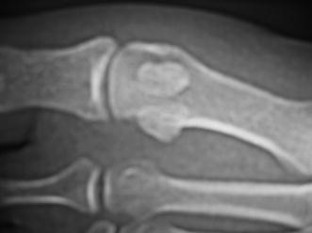

Fig. 1